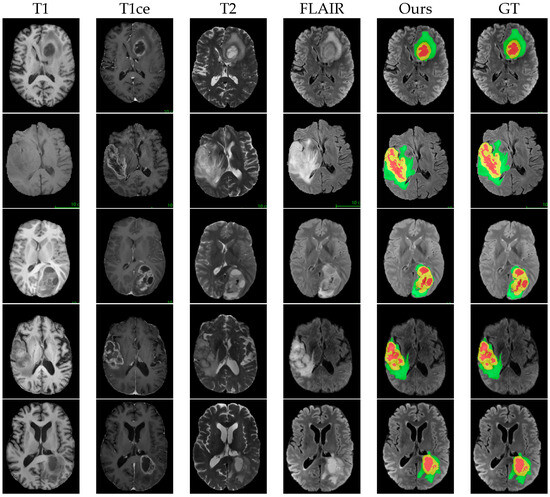

4.4. Comparison with Other Methods